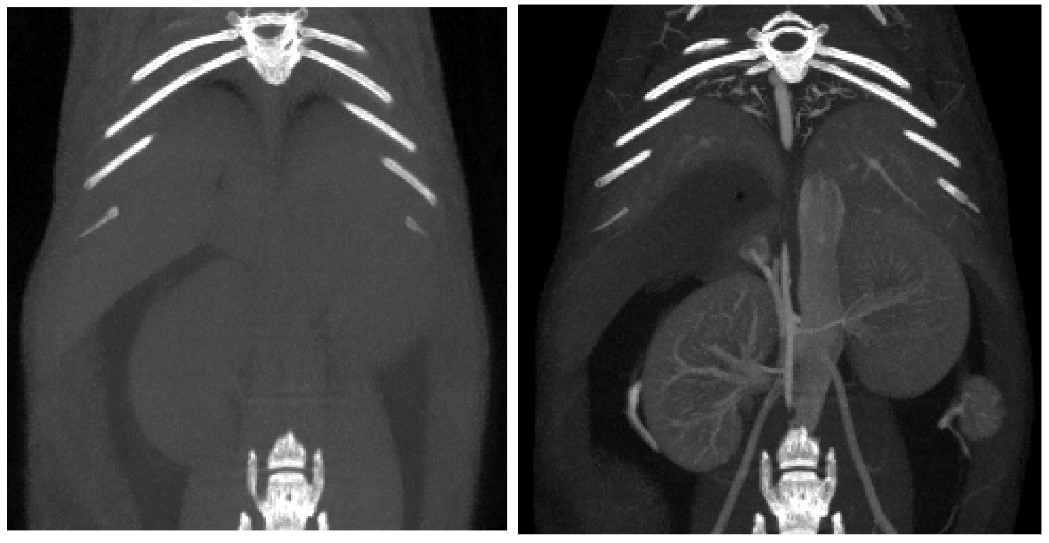

Tumor study: Contra-enhanced CT was used to examine liver tumors in living mice: Exitron 12000 was injected, FDK was reconstructed, and the imaging time was 4min, 100µm voxel size.